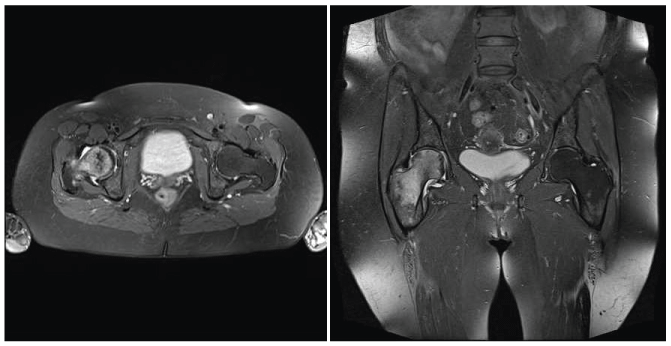

Considering the patient still experienced pain upon weight-bearing, on the follow-up examination, a diagnostic ultrasound (US) of both hip joints was performed by the physiatrist (Figure 1). Significant effusion of the right hip joint led to a magnetic resonance imaging (MRI) of both hip joints (Figure 2). The MRI revealed an ischemic lesion of the entire head and neck of the right femur with edema, including slight applanation of the femoral head and a small subchondral fracture (Steinberg classification system, grade I). Upon consultation with an orthopedic surgeon, the patient was referred for HBOT. Consequently, this choice of therapy was proposed for two months after the initial symptoms appeared.

Figure 2: MRI of both hip joints. Subchondral fracture of the right femoral head, an ischemic lesion and edema of the right femoral head and neck (left side of picture). Axial and coronal images in T2. View Figure 2